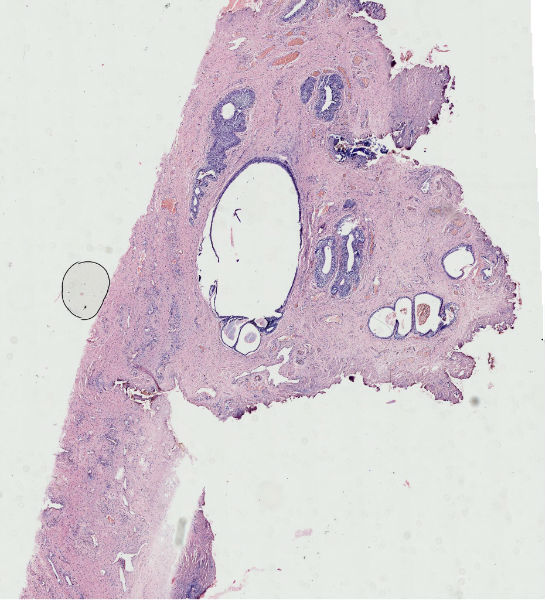

女57岁发现尿道外口息肉二周

图1